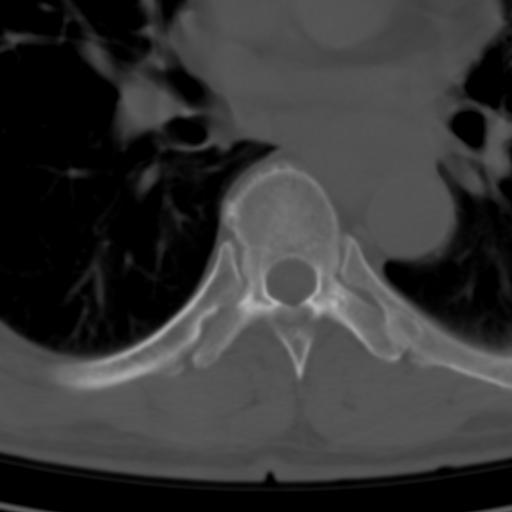

标题: CT25189:胸椎ct,请会诊!

既往食管癌,现行ct检查!

中上段食道癌,椎体轻度退变。

椎体退行性改变,食管癌。